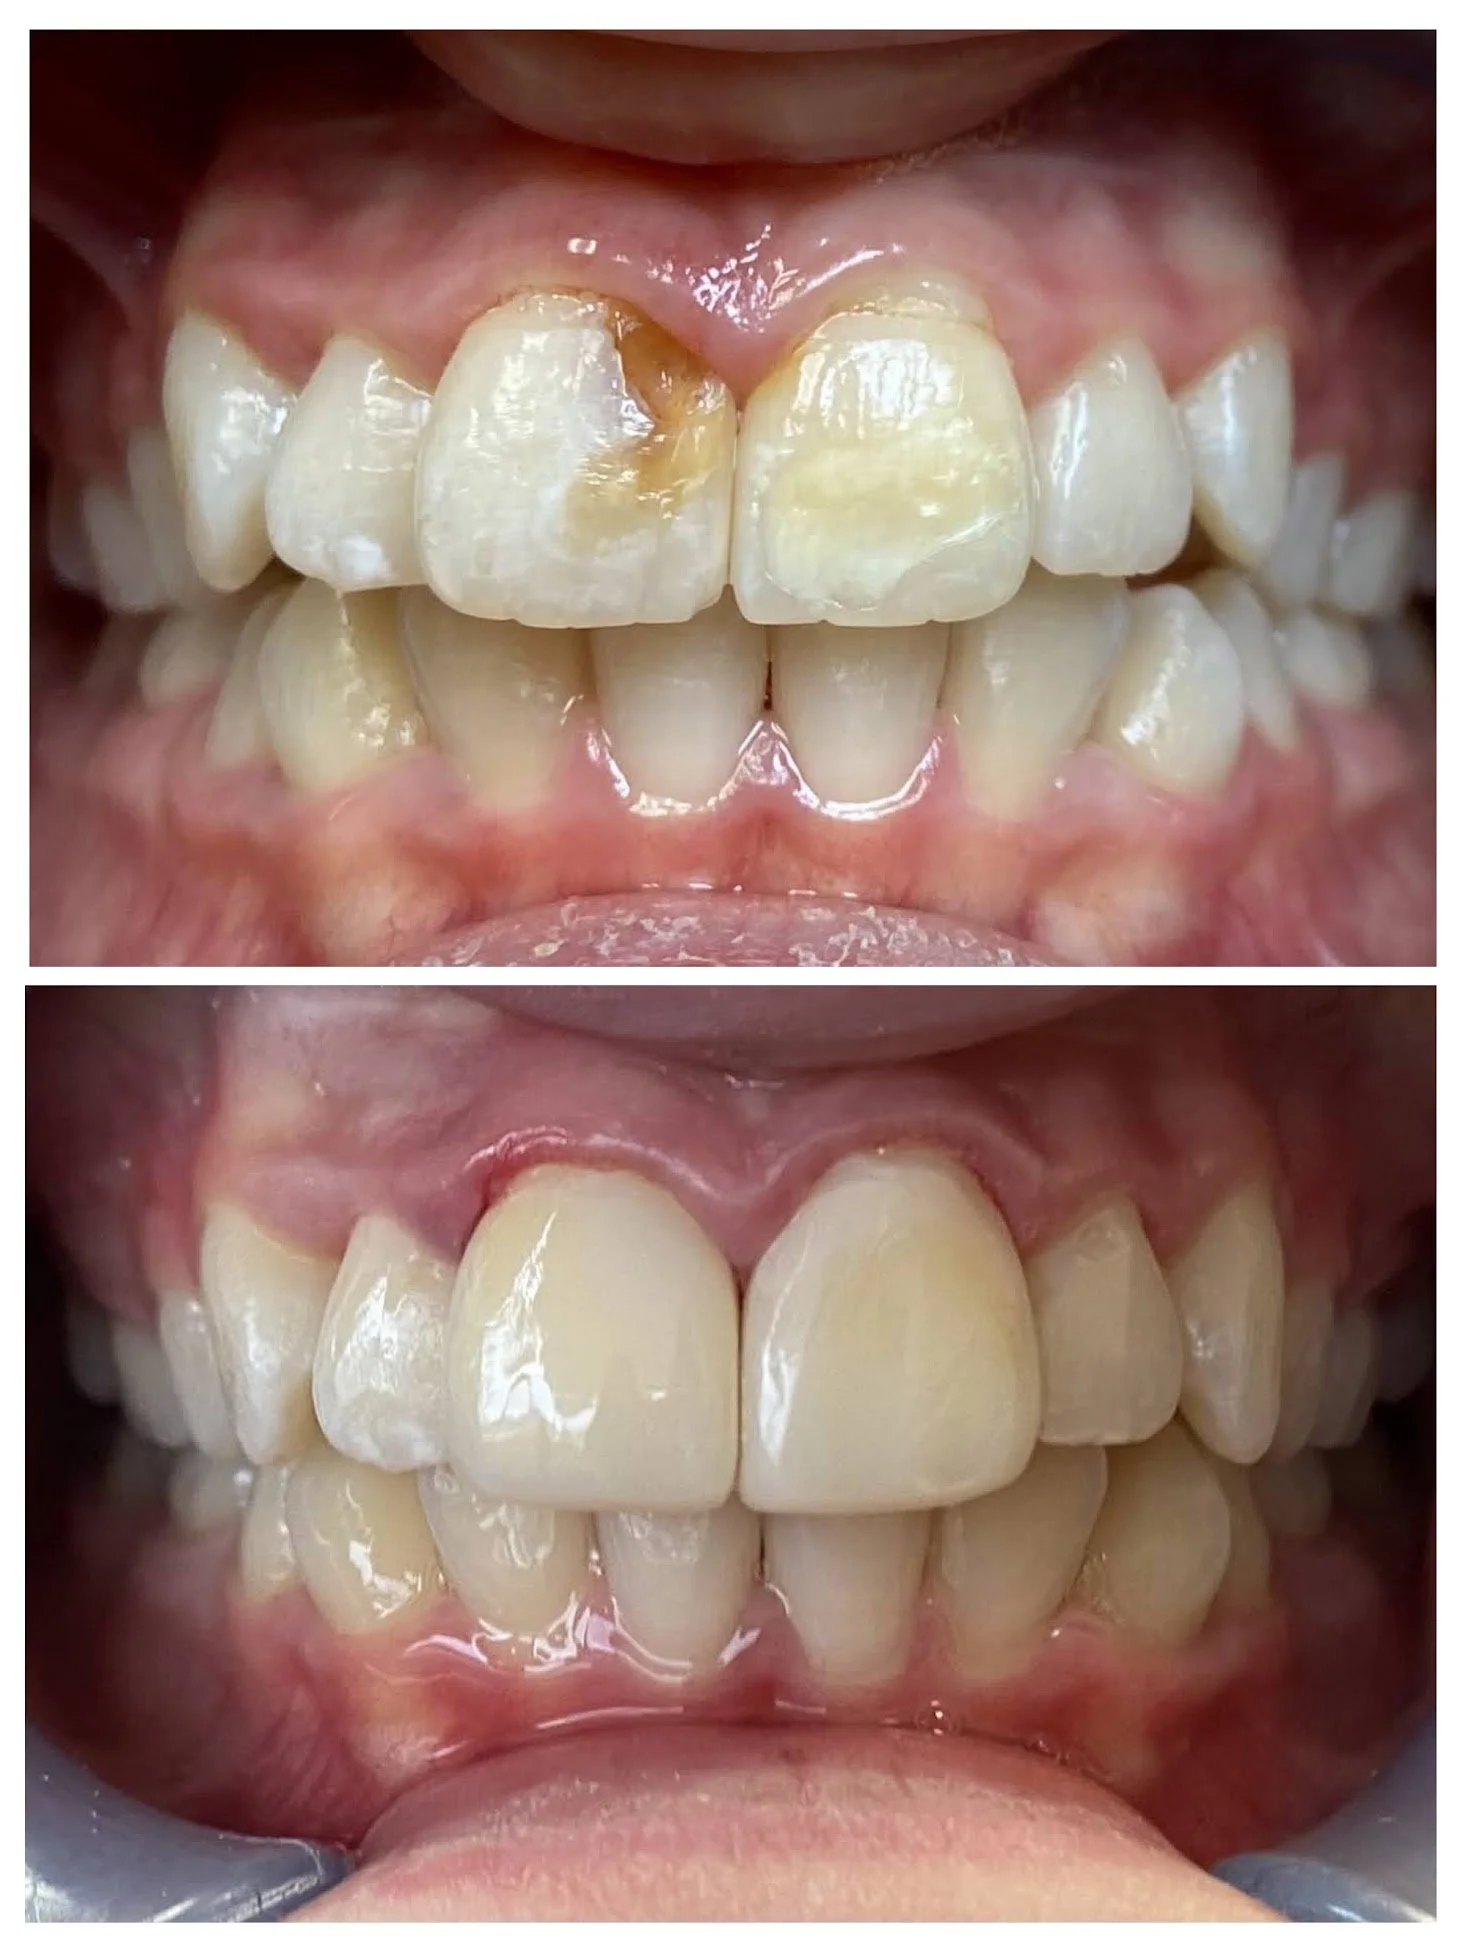

Crowns